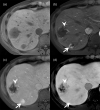

MRI is widely used in clinical practice for detecting liver diseases. Since the introduction of gadoxetic acid, MRI has become the most effective modality for the detection and characterization of focal liver lesions. According to previous meta-analyses, the area under the receiver operating characteristic curve (AUROC) was 0.97-0.99 for the diagnosis of small hepatocellular carcinoma (≥ 2 cm) by gadoxetic-acid-enhanced MRI. Moreover, the AUROC for the diagnosis of colorectal liver metastases was significantly high (0.98). Despite gadoxetic acid's drawbacks, its clinical utility outweighs them, making it the contrast agent of choice in routine liver MRIs. Moreover, clinically, liver MRI has become more prevalent for a quantitative assessment. Liver fibrosis can be evaluated using MR elastography; whereas, hepatic steatosis and iron overload can be evaluated using proton density fat fraction, with high accuracy and reproducibility. This article reviewed the usefulness of liver MRI, which can be a comprehensive imaging modality in clinical practice.